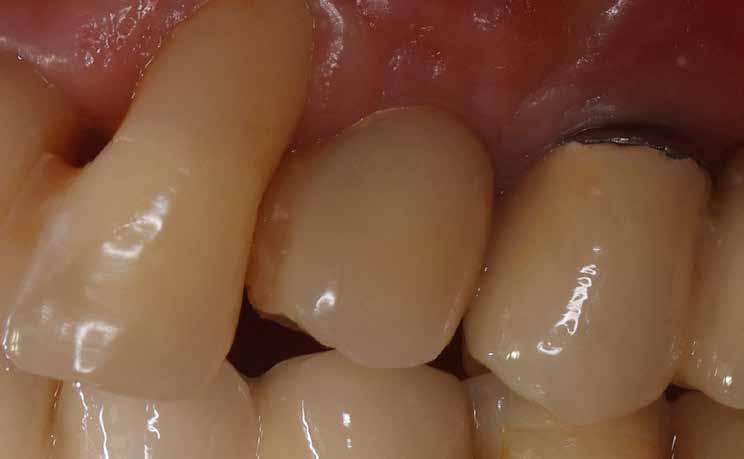

A 2020 januárjában elkezdett kezeléssorozat befejezését az év márciusában, hazánkba is begyűrűző Covid-19 pandémia késleltette, így kb. 6 hónap gyógyulás után láttunk hozzá az emergencia profil és a gingivális zenit ideiglenes koronával történő formázásához (11. és 12. kép). A 3 hetente végzett apró alakításokkal sikerült megfelelő ínyprofilt kialakítani, a „rózsaszín esztétika” a páciens számára is megfelelő volt. A bal felső nagymetsző fog meziális kompozit tömés cseréjét követően, individualizált nyitott kanalas lenyomati fejet készítettünk: az akrilát ideiglenes korona profilját átlátszó szilikonnal lemásoltuk, majd a körszimmetrikus gyári lenyomati fej és az ideiglenes korona kontúrja közötti hézagot folyékony kompozittal töltöttük ki (13. kép). Az így készített egyéni lenyomati fejjel vettünk lenyomatot a végleges, kerámialeplezésű cirkónium-dioxid vázas, átmenő csavaros rögzítésű koronához. (A fogtechnikai munkát Nébl Péter fogtechnikusmester készítette.), (14., 15., 16 és 17. képek).

A kész korona átadásakor a páciens elégedett volt az esztétikával, az azóta eltelt évben rendszeres kontrollokon jelent meg, melyek során meggyőződtünk a kemény- és lágyszövetek stabilitásáról (18. és 19. képek).